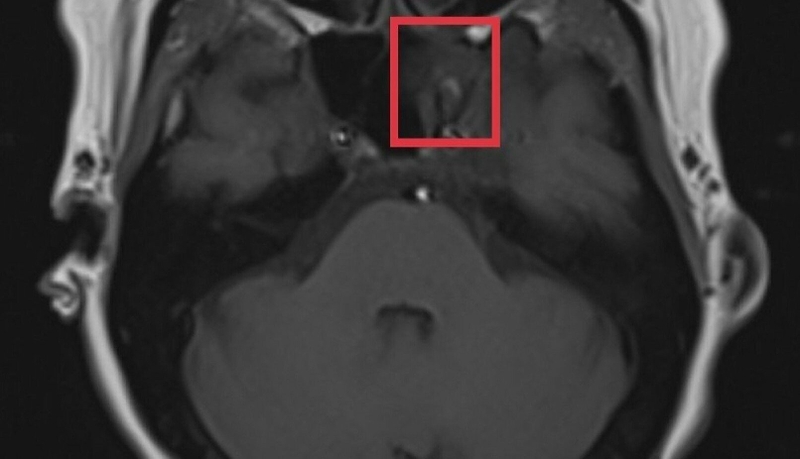

Ngoài ra, còn có một dạng nang nhầy khác có kích thước tương đối lớn và vỏ nang trong suốt giống với bụng con nhái nên được gọi là nang nhái. Nang nhái thường chỉ xuất hiện ở sàn miệng một bên, hình thành do tắc nghẽn tuyến nước bọt dưới lưỡi hoặc các tuyến nước bọt phụ ở sàn miệng.